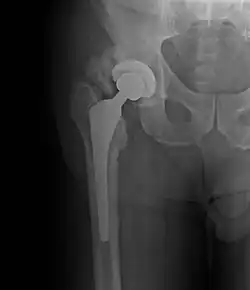

• Hip most common - typically after ORIF (52% any grade, 19% Grade III-IV) or THA (43% any grade, 9% Grade III-IV)

Brooker Classification: (radiographic)

• I - islands of bone within the soft tissue (clinically silent)

• II - bone spurs from the pelvis or proximal femur; >= 1 cm gap between opposing surfaces (clinically insignificant)

• III - bone spurs from the pelvis or proximal femur; < 1 cm gap between opposing surfaces (clinically significant)

• IV - ankylosis (clinically significant)